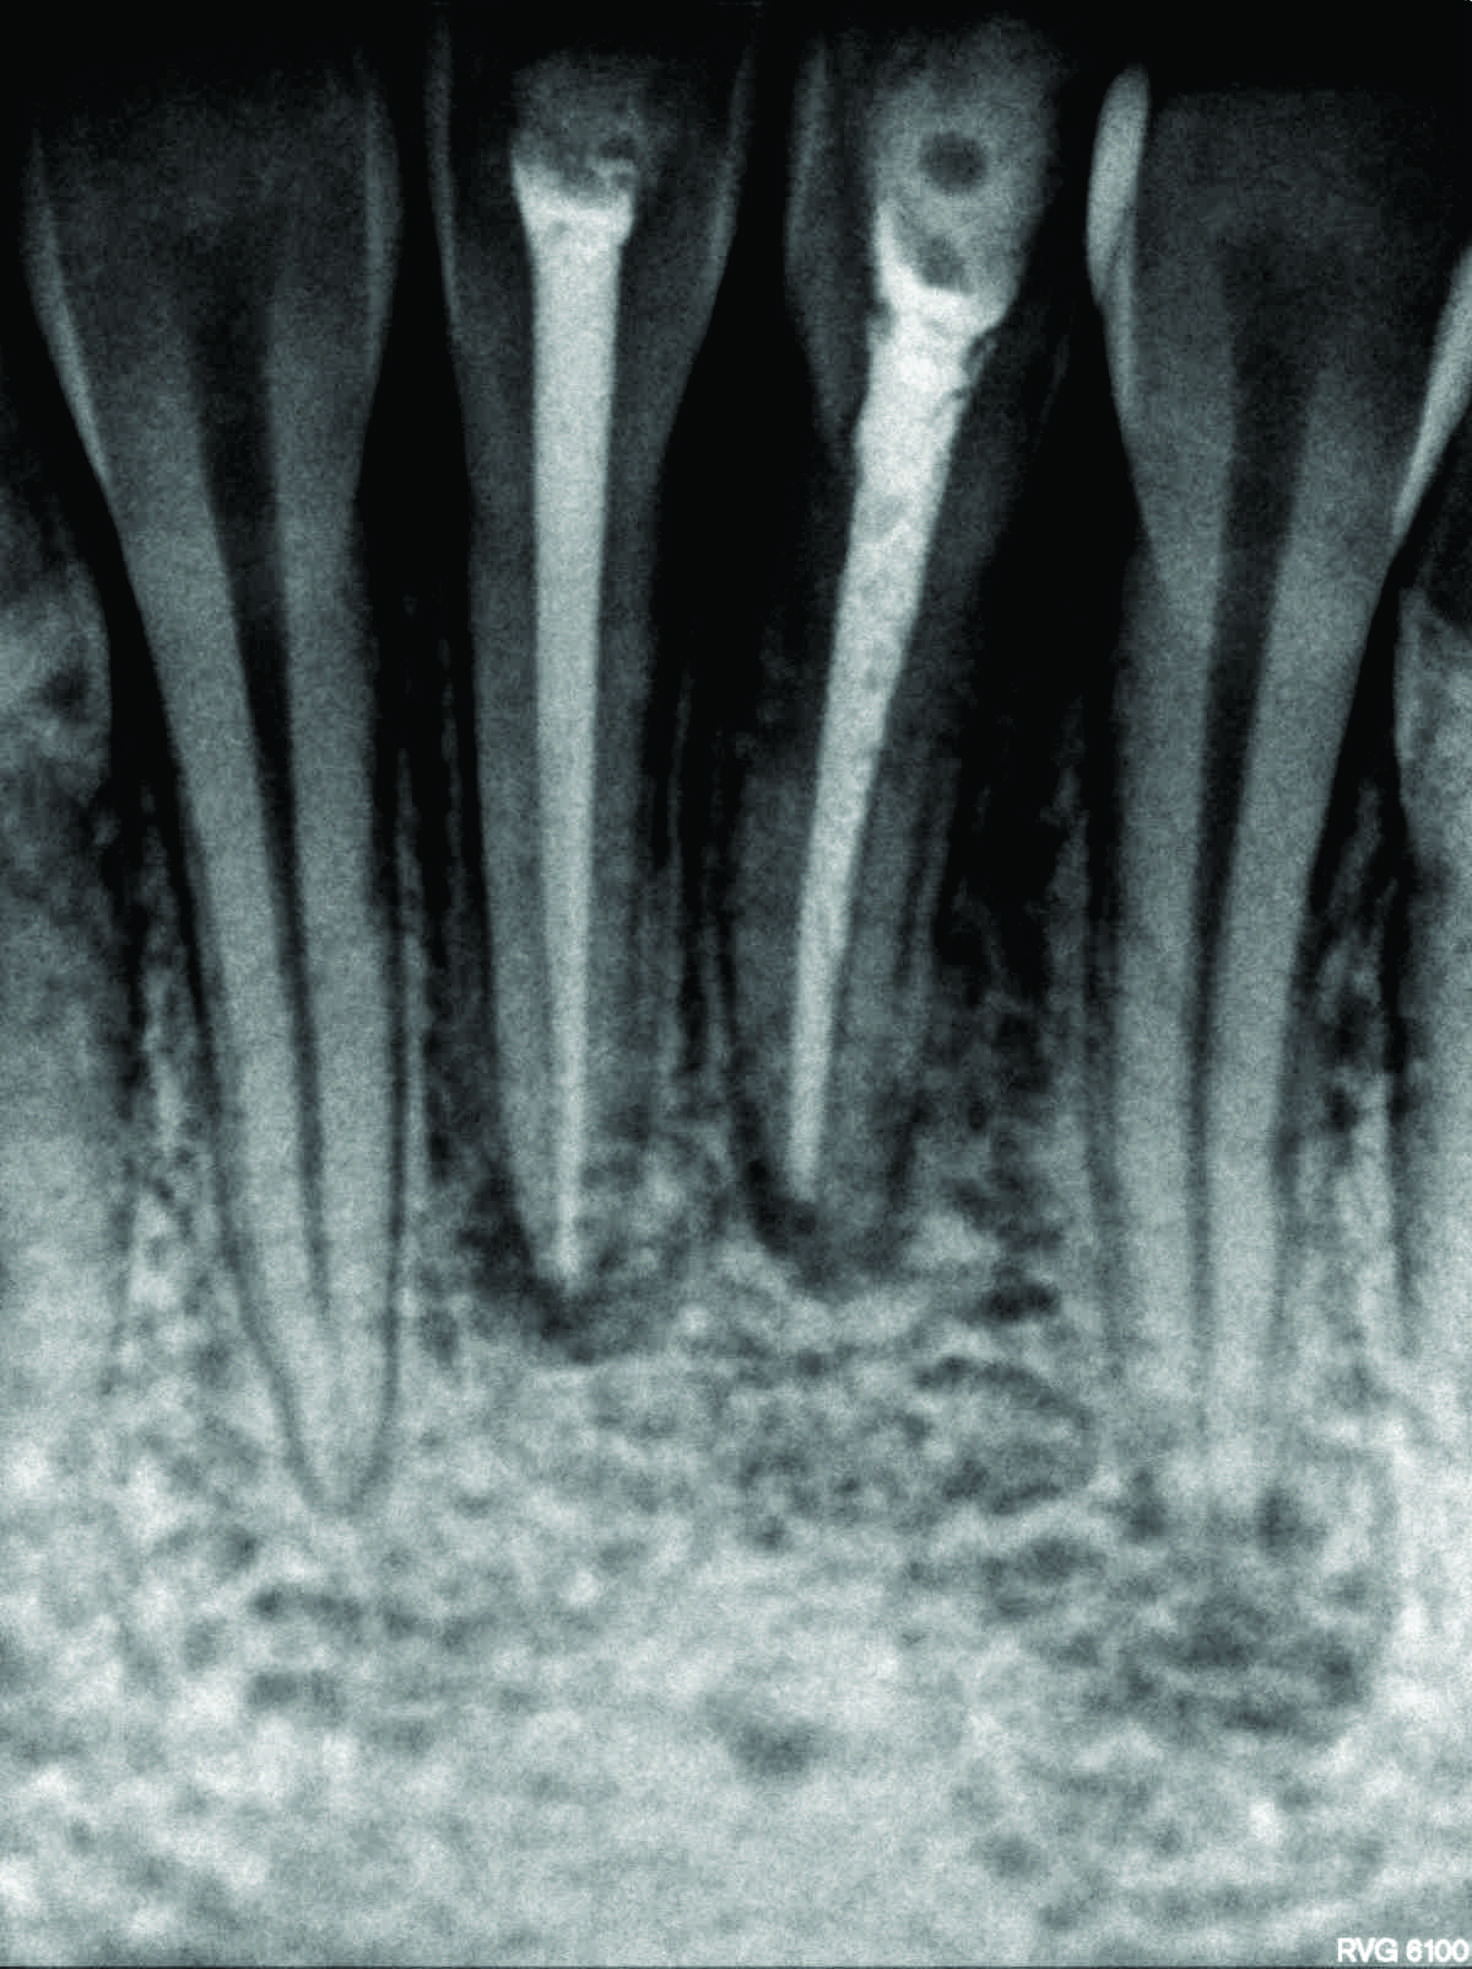

The cutaneous sinus healed following root canal treatment and antibiotic coverage. On an 8-year follow-up skin of sub-mental region appeared normal and peri-apical healing with both mandibular central incisors was evident radiographically. Cutaneous lesions on face may be of dental origin. A cross referral between dentists, physicians, surgeons, and dermatologists should be considered in such cases.